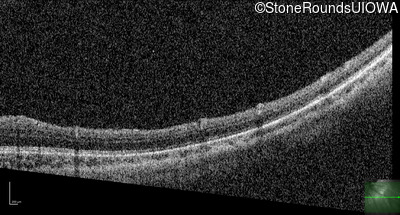

Optical Coherence Tomography - Right - 20/2000

Exemplar / OCT Stack

Optical Coherence Tomography - Left - 20/80